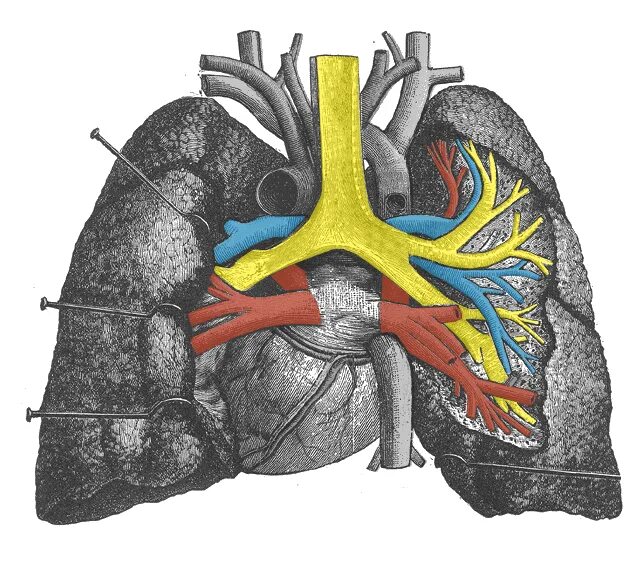

Легочный ствол легкого